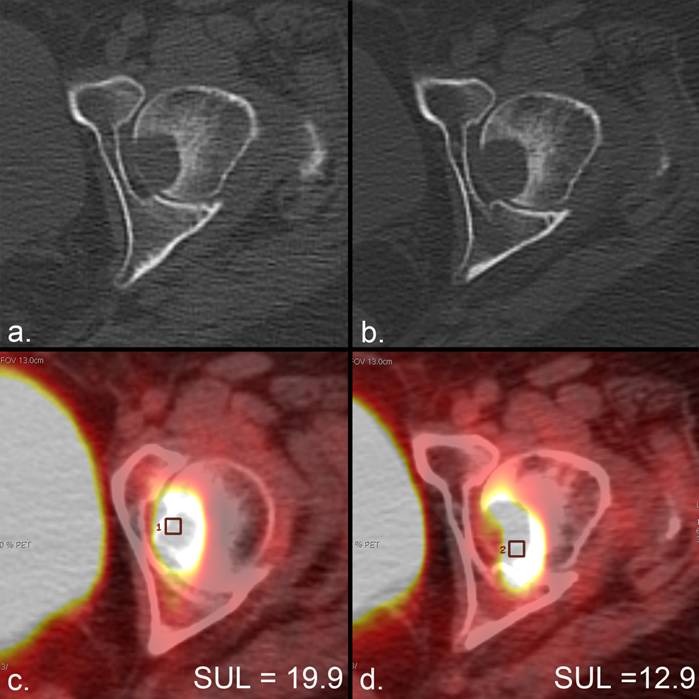

PERCIST defines 4 response categories (Table 3) in addition to plotting tumor response in weeks from the initiation of therapy. Complete metabolic response is defined as the disappearance of metabolic tumor activity in target and nontarget lesions. Residual FDG uptake can be seen despite effective therapy, possibly due to macrophage activity (62), and therefore PERCIST define complete metabolic response as a decrease in tumor SUL to the level of surrounding normal tissue. Partial metabolic response is defined by a decline of > 30% in SUL peak with at least a 0.8-unit decline (Fig. 10). Progressive metabolic disease includes an increase of > 30% in SUL peak with at least a 0.8-unit increase, a visible increase in the extent of FDG uptake (increase in the color field representing FDG uptake), or the development of new lesions. In the absence of clear evidence of disease progression on the fused CT image, new FDG-avid foci are to be verified on a follow-up scan 1 month after discovery. Stable metabolic disease is the absence of change or mild changes that do not meet the minimum qualifications of the other categories. Anatomic change in tumor size remains an important factor under PERCIST and is to be measured according to RECIST 1.1. If lesions increase or decrease in size without a corresponding change in metabolic activity, disease progression or response is to be verified on a follow-up scan.

Figure 10

Metabolic response according to the PERCIST criteria in the absence of anatomic response. (a) The CT portion of an FDG PET/CT scan in a patient with lung cancer demonstrates a lytic metastasis in the left femoral head. (b) The CT from a PET/CT scan 2 months later demonstrates no anatomic change. (c, d) The standardized uptake value corrected for lean body mass (SUL) peak (average SUL in a 1-cm3 region of interest centered at the most active part of each tumor) changes from (c) 19.8 to (d) 12.9, representing a 35% decrease that satisfies the minimal requirements for partial response (> 30%) according to PERCIST. Assessment of tumor metabolism allowed therapeutic response to be measured in the absence of any other indication of change.